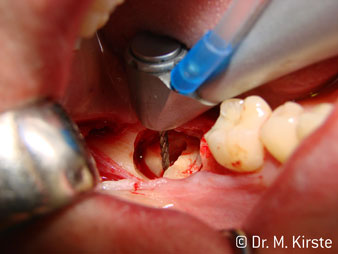

The 45° angle of the handpiece has been specially selected for its wide range of advantages. Colleagues who work in surgery, and for whom this handpiece was primarily developed, will soon appreciate the ability to work efficiently in very restricted spaces. In wisdom tooth extractions in particular (fig. 2) there is no need for large-scale spreading of the soft tissues in the cheek region (fig. 3). The design of the handpiece head combined with turning the head slightly during preparation allows work to be carried out quickly and safely in the retromolar region.

The professional design of the bearings inside the handpiece head guarantees quiet running of the bur; this makes for an impressively atraumatic cut in the separation of tooth and root (fig. 4-9).

Fig. 3